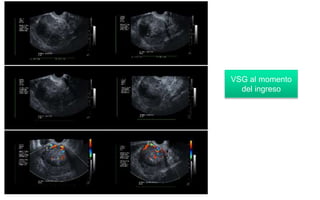

VSG al momento

del ingreso